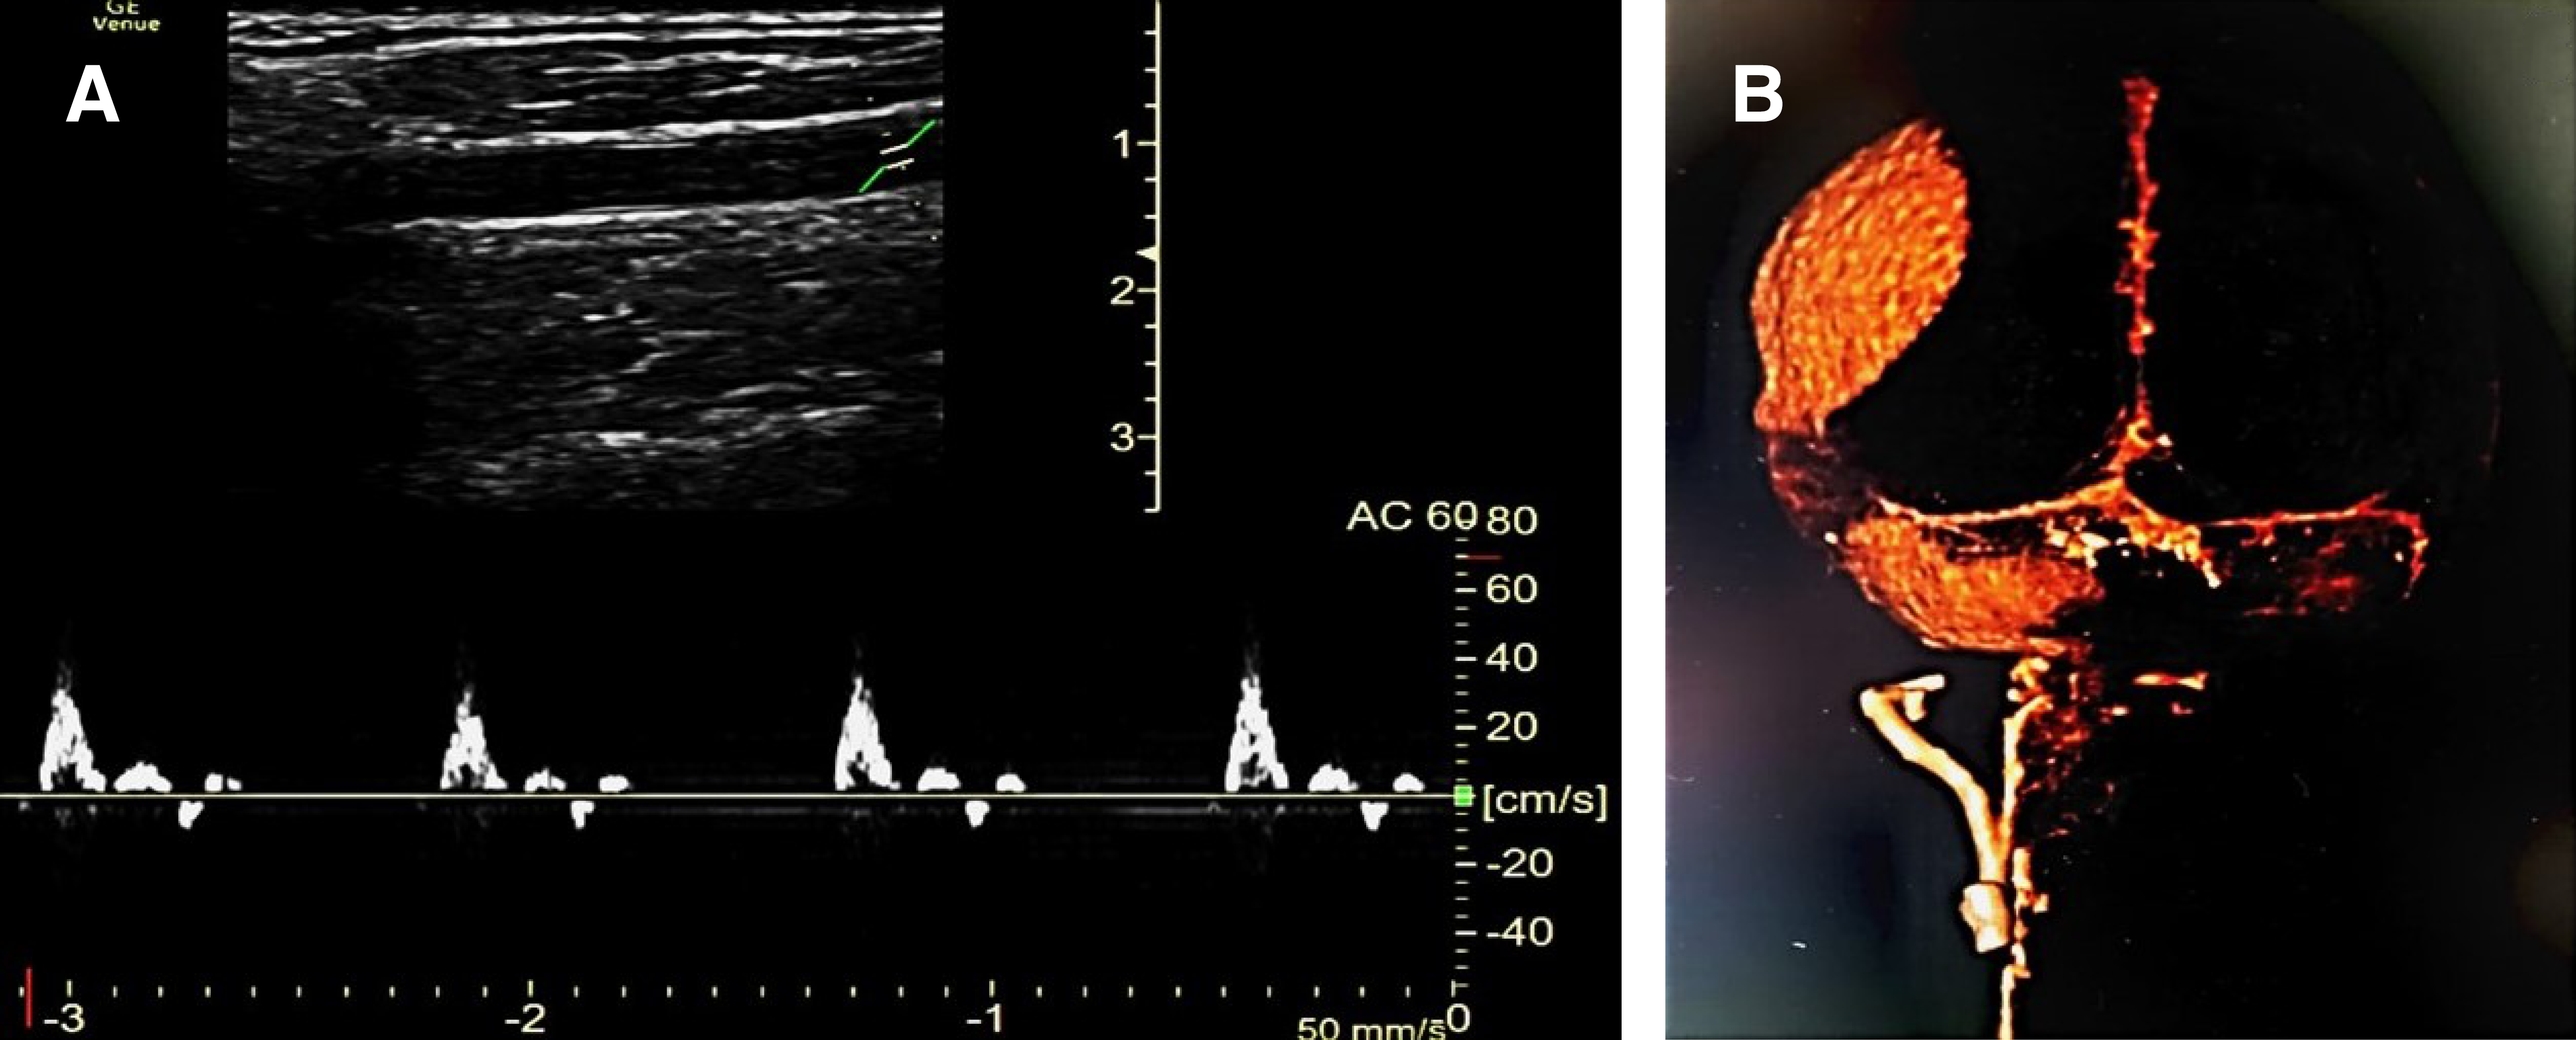

Uso de ultrasonido Doppler carotídeo en muerte encefálica. El estudio Doppler de la ACC se realiza con un transductor lineal con frecuencia de 7-14 MHz en modo bidimensional y posteriormente con PW, con el cual se evalúa el espectro de la velocidad de flujo diastólica y sistólica. El espectro Doppler de la ACC es monofásico, con un componente diastólico bien delimitado y con un patrón de bajas resistencias y una velocidad sistólica máxima no mayor de 100 cm/s.7,8

Con base en el consenso de guías CARE se desarrolla un reporte de caso observacional y descriptivo. Se incluyen dos pacientes con diagnóstico de muerte cerebral ingresados en la Unidad de Cuidados Intensivos del Hospital General de San Juan del Río, donde evaluamos, con un equipo de ecografía Venue R2 General Electric 2.0 empleando un transductor lineal de 7.5 Hz y PW, cambios en el flujograma de la arteria carótida interna en la región extracraneal (ACIe) y la carótida común (ACC). Presentamos dos casos de MC confirmada con evidencia de alteraciones en el patrón del ultrasonido Doppler en la ACC y ACIe.

Caso 1. Hombre de 17 años que es traído por personal prehospitalario a la sala de emergencias el 19 de diciembre de 2021 tras sufrir un accidente de motocicleta con diagnóstico de lesión cerebral traumática. A su ingreso presenta pupilas de 4 mm de diámetro y reflejo fotomotor disminuido con un puntaje en la escala de coma de Glasgow de 7, se realiza secuencia de intubación rápida y ventilación mecánica invasiva, en la tomografía de cráneo se observa un hematoma epidural parietoccipital derecho que desvía la línea media hasta 10 mm más hemorragia cerebelosa derecha con compresión del tallo cerebral. El estudio de gases arteriales se reporta un pH de 7.5 y presión parcial de dióxido de carbono arterial de 21 mmHg. El día 20 de diciembre presenta midriasis bilateral y ausencia de reflejo fotomotor, por lo que se inicia protocolo de MC, se retira la sedación y se realiza DTC, en el cual se observa ausencia de flujo en el polígono de Willis en ventana transtemporal bilateral por dos observadores entrenados, posteriormente se realizó un ultrasonido Doppler en ACC y ACIe observando espigas sistólicas de 45 cm/s con patrón oscilante y ausencia de flujo diastólico (Figura 2). La MC se corroboró por angiotomografía cerebral. Los familiares no aceptan donación de órganos, por lo que se retira el soporte multiorgánico.

Caso 2. Mujer de 63 años con antecedente de diabetes e hipertensión arterial sistémica, admitida en la unidad de cuidados intensivos (UCI) el 30 de noviembre de 2021 por COVID-19 crítico con síndrome de distrés respiratorio agudo severo. La paciente fue sometida a traqueostomía el día 17 de diciembre por ventilación prolongada y ese mismo día presenta secreciones bronquiales abundantes y coágulos que ocasionan obstrucción en la vía aérea y arresto cardiaco por hipoxia por aproximadamente cuatro minutos, posterior al retorno de la circulación espontánea presenta hipoxemia sostenida con saturación de oxígeno arterial (SpO2) de 80% a pesar de una fracción inspirada de oxígeno al 100% y presión positiva al final de la espiración de 8 cmH2O. La paciente es encontrada durante la guardia nocturna del 20 de diciembre con midriasis bilateral de 8 mm de diámetro sin reflejo fotomotor, por lo que se inicia protocolo para descartar MC. Se realiza USG en la ACC, observando espigas sistólicas con velocidad de 45 cm/s y patrón oscilante con ausencia de flujo diastólico, posteriormente se realiza DTC, en el cual se observa ausencia de flujo en el polígono de Willis y circulación posterior corroborando la MC (Figura 3). La paciente no es candidata a donación de órganos por disfunción multiorgánica, por lo que se suspende el soporte de vida.

En los casos expuestos anteriormente identificamos imágenes con patrones ecográficos similares a los descritos por Yoneda y colaboradores observando en el espectro Doppler flujo diastólico retrógrado a nivel sólo de la ACC, a diferencia de Mehrdad y su equipo que también analizaron la ACIe aumentando la sensibilidad para el diagnóstico de MC. En nuestros casos corroboramos el patrón descrito de forma bilateral a nivel de las ACC y las ACIe encontrando picos sistólicos anterógrados de baja velocidad y ondas diastólicas retrógradas de velocidad aún menor.